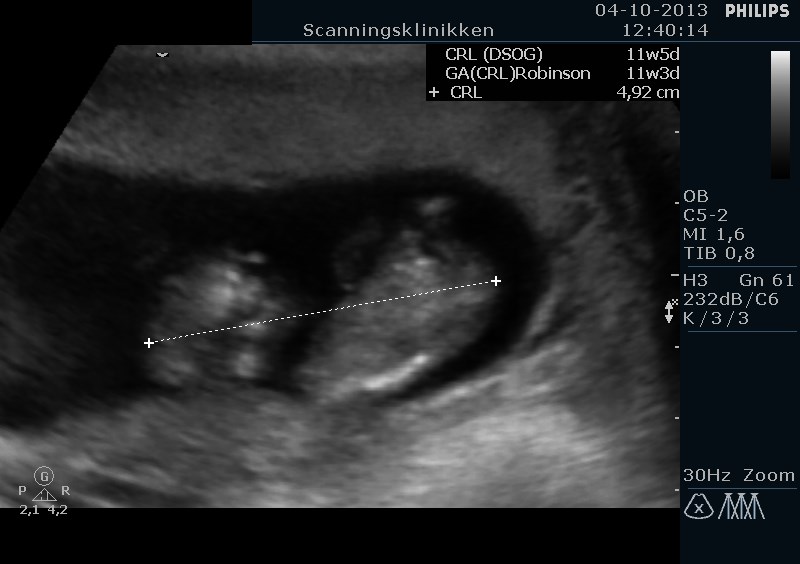

Men se lige hvad vi har set i dag. En lille spire på næsten 5 cm og er 11+5 uger henne med en termin den 20 April <3